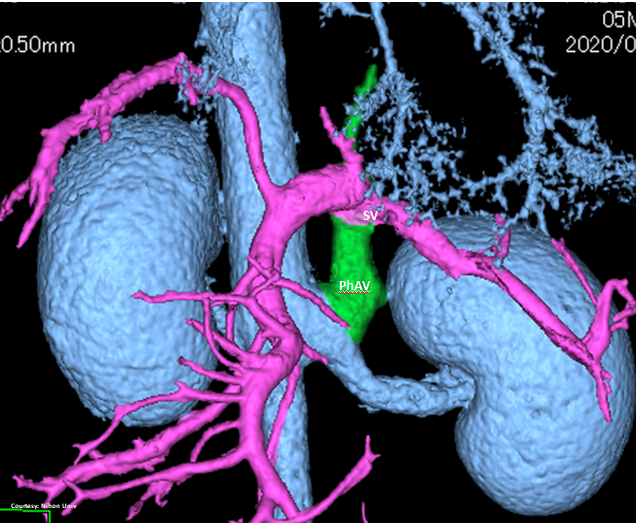

PRE-HEPATIC ENTRANCE

(Absent GSV)

“LGC +PancV -GSV” Left Gastro-Caval Shunt with Pancreatic Vein contribution and absent Gastro-splenic vein (GSV does not enter PV)

Courtesy: Nihon Univ

WEISSE 2022